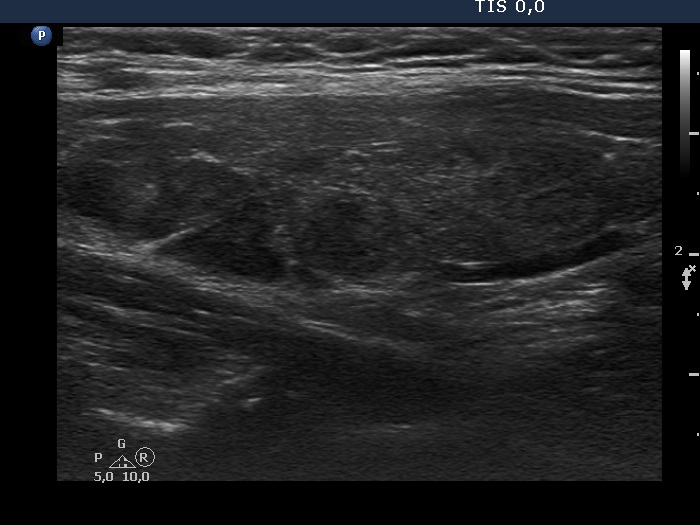

Consecutive patients with the final diagnosis of Hashimoto's thyroiditis - case 57 (774) (ultrasonographic picture 9)

Left lobe, longitudinal scan. There are more hypoechogenic fields in the dorsal part of the lobe.